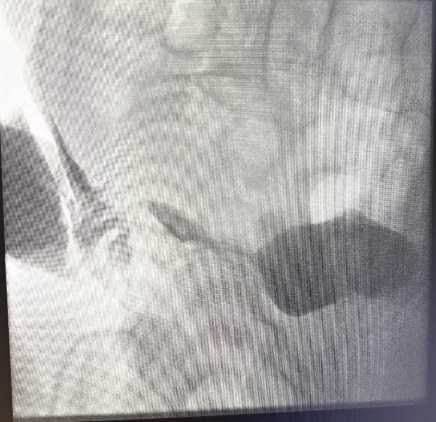

A 70-year-old male with a history of ischemic heart disease managed with a proximal LAD stent, and ongoing treatment with aspirin, atorvastatin, candesartan, and lansoprazole, underwent elective laparoscopic totally extraperitoneal (TEP) right inguinal hernia repair. The procedure was initially uncomplicated. Three years later, he presented with visible haematuria and right-sided abdominal pain. Cystoscopy revealed a 5 mm lesion on the right anterior bladder wall with floating debris, and although imaging excluded urinary obstruction, bowel inflammation raised concerns for possible Crohn’s disease (no previous evidence). The lesion was deemed benign, and he was referred to surgery for evaluation of groin discomfort. Shortly thereafter, he developed a right groin abscess, confirmed on CT and managed twice with ultrasound-guided drainage by interventional radiologist and antibiotics. However, symptoms recurred with ongoing purulent discharge from the suprapubic region. Further imaging revealed displaced mesh embedded within a heterogeneous collection. The patient remained systemically well but required readmission due to persistent wound drainage. A repeat CT (Figure 1) scan showed inflammatory collections in both the inguinal and pelvic regions, with compression of the urinary bladder and associated soft tissue changes. Urgent operative exploration revealed a chronic abscess cavity communicating with the mesh site; the mesh was partially floating and surrounded by infected granulation tissue. The sinus tract was excised, the cavity debrided, and the mesh removed (Figure 2). Postoperatively, the patient developed high-volume serous fluid output through the wound. An urgent cystogram was requested by the urology team after the referral confirmed a vesico-cutaneous fistula originating from the bladder base and tracking to the suprapubic wound (Figure 3). Conservative management with an indwelling urinary catheter was initiated with the urology team’s advice. Despite intermittent haematuria and cloudy discharge, the patient remained clinically stable and was managed with antibiotics. On follow-up cystography, no further leakage was observed, and the fistula was deemed healed, though mild left-sided ureteric reflux persisted (Figure 3). The patient was scheduled for uroflowmetry, and a bladder scan to assess function, and a telephone follow-up was arranged to monitor long-term outcomes. He has also been discussed in both surgical and urological Mortality and Morbidity meetings.

Figure 3. Cystogram images before and after catheter insertion. The initial image demonstrates contrast extravasation from the right bladder base to the anterior abdominal wall, confirming a vesico-cutaneous fistula. The follow-up image shows no contrast leakage after prolonged catheter drainage, indicating fistula resolution.

• Cystographic Evaluation

Contrast cystography revealed that Urografin contrast leaked from the right bladder base, tracking laterally and exiting through a cutaneous sinus—confirming the presence of a right-sided vesico-cutaneous fistula. There was no evidence of vesico-ureteric reflux at that time.

• Serial Imaging and Recovery Monitoring

As part of conservative management, subsequent imaging demonstrated significant reduction in abscess size, with a residual fluid pocket of ~15 mm and persistent, but improving, inflammatory changes. A repeat cystogram later showed no active urine leak, suggesting spontaneous closure of the fistula tract. However, mild right-sided ureteric reflux was incidentally noted on imaging, located on the same side as the prior fistula. This was not clinically significant and required no further intervention.